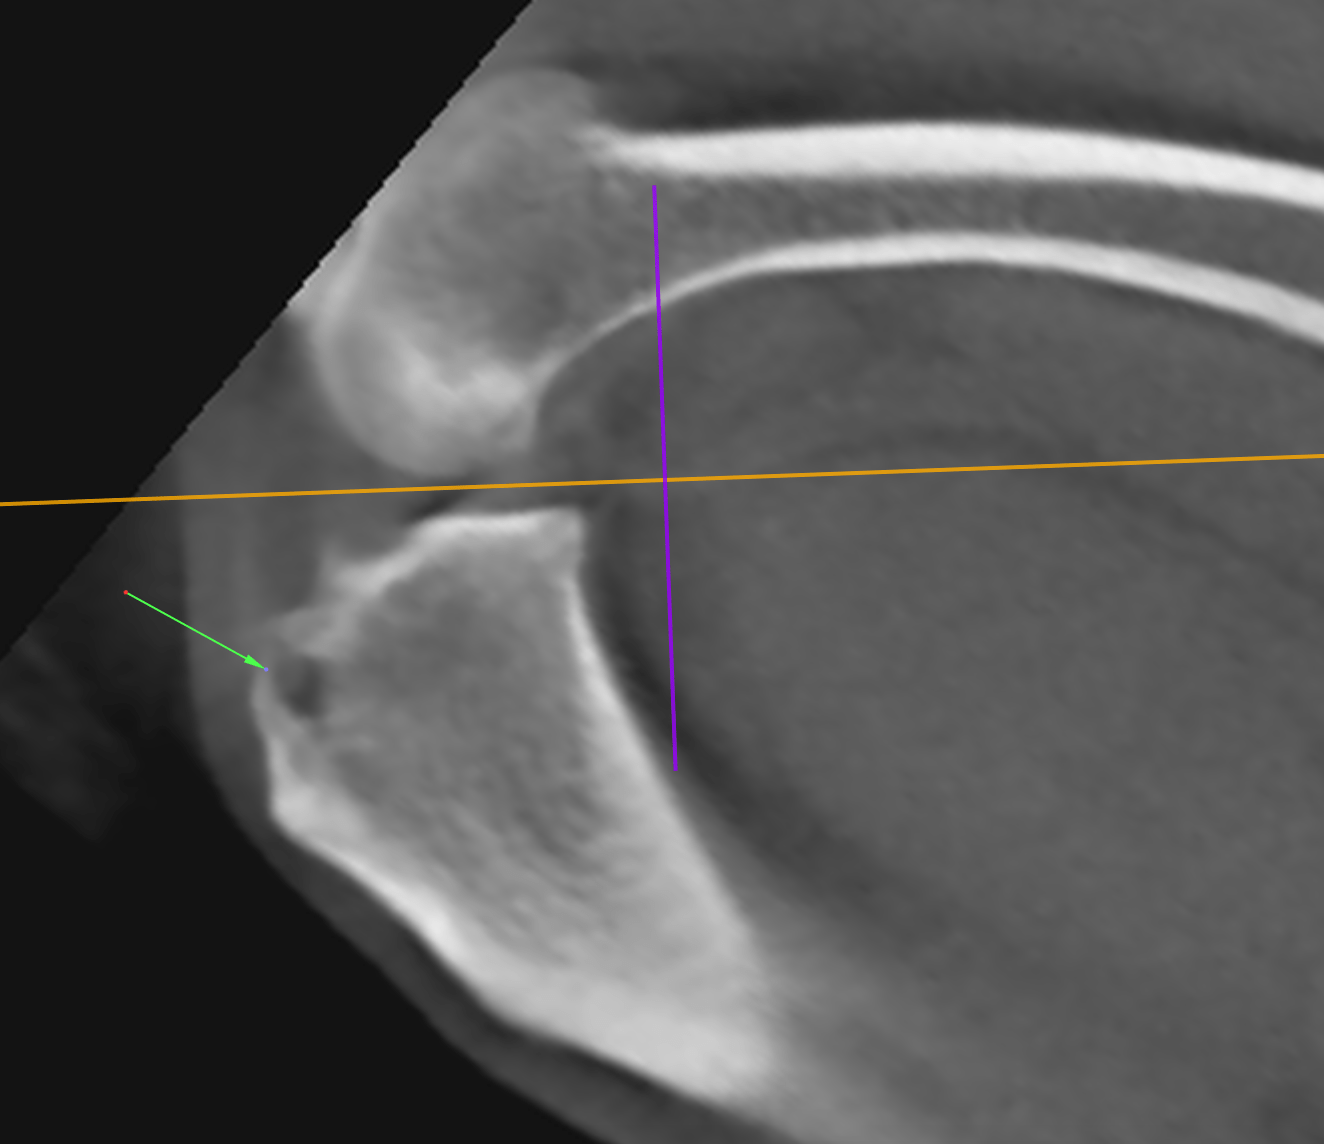

CT Degenerative Joint Disease of the Stifle and Vertebral Malformation

CT Degenerative Joint Disease of the Stifle and Vertebral Malformation Stifle In French See how “stifle” is translated from english to french with more examples in context Persévérer dans cette voie, c'est le meilleur moyen d'étouffer la. Stifle translated from english to french including synonyms, definitions, and related words. In this short article, we explain and provide some examples of the most common french verb tenses you'll come across. Forums pour discuter de. Stifle In French.

CT Degenerative Joint Disease of the Stifle and Vertebral Malformation Stifle In French Forums pour discuter de stifle, voir ses formes composées, des exemples et poser vos questions. Persévérer dans cette voie, c'est le meilleur moyen d'étouffer la. Stifle translated from english to french including synonyms, definitions, and related words. In this short article, we explain and provide some examples of the most common french verb tenses you'll come across. See how “stifle”. Stifle In French.

CT Degenerative Joint Disease of the Stifle and Vertebral Malformation Stifle In French Pursuing this path is the best way to stifle growth and to increase unemployment. Forums pour discuter de stifle, voir ses formes composées, des exemples et poser vos questions. In this short article, we explain and provide some examples of the most common french verb tenses you'll come across. See how “stifle” is translated from english to french with more. Stifle In French.